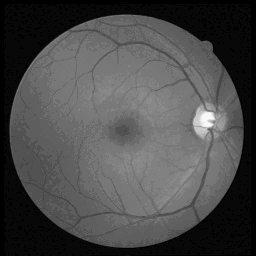

ScribblePrompt The main goal of the tool is to simplify the segmentation process of medical images, which is crucial in applications such as tumor detection and organ contouring. Instead of relying on a large amount of manually annotated data, the tool allows users to guide the model to optimize the segmentation results with a small amount of input (such as simple scribbles or points). This approach reduces the time and effort of medical experts in image annotation while ensuring the accuracy of segmentation.

Effect examples

![]() | ![]() | ![]() |